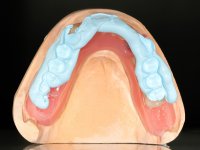

Two dental implants were planned in the CBCT scan, in the area of the inferior canines. The dental extractions were performed and, simultaneously, the alveolar crest was flattened and the implants were placed. Three issues were considered while implant placement: parallelism of the axis, same height of the implant’s neck, and same position in the coronal plan. This 3D insertion is essential to have a good retention of the overdenture in the future. Patient’s removable denture was fixed in the dental lab, to include the extracted teeth, and a soft-tissue relining was done over the healing abutments. After the osseo-integration period, a first impression was done with an open-tray and a doble-mix technique. This dental impression allowed the production of screwed wax-rims and an individual tray for a functional impression. A second impression, final, was done with an individual tray with a monophasic silicone. The occlusal wax-rims were correct in the mouth according to the full denture guidelines. Special care was taken with the occlusal vertical dimension and the support in the soft-tissues. A silicone bite registration material was used to better defined the intermaxillary relations. Teeth set-up was done in the dental lab with the selected tooth color. Due to the fact that the base was screwed to the dental implants, the teeth set-up was functionally evaluated in the mouth. Another silicone bite registration material was used to allow final occlusal adjustments. Finally, the locators were screwed and the retention nylons were selected according to the patient needs.